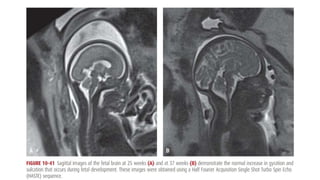

• 10.41

MAGNETIC RESONANCE IMAGING •The fetus was first studied with MR imaging in the mid-1980s, when image acquisition was slow and motion artifact was problematic • Since then, technological advances that allow fast-acquisition MR protocols have been developed • Image resolution with MR is often superior to that with sonography because it is not as hindered by bony interfaces • MR may be a useful adjunct to sonography in evaluating and further characterizing suspected fetal abnormalities.

• #12 These newer protocols permit image acquisition in 1 second or less, which significantly reduces motion artifact and eliminates the need for sedation MR imaging, however, is not portable, it is time-consuming, and its use is generally limited to referral centers with expertise in fetal imaging. It may be helpful in the evaluation of complex abnormalities of the fetal CNS, thorax, gastrointestinal system, genitourinary system, and musculoskeletal system MR has also been used in the evaluation of maternal pelvic masses, placental invasion, and abnormalities of the pelvic floor and cervix The American College of Radiology and Society for Pediatric Radiology (2010) have developed a practice guideline for fetal MR imaging. This guideline acknowledges that sonography is the screening modality of choice. Moreover, it recommends that fetal MR imaging be used for problem solving to ideally contribute to prenatal diagnosis, counseling, treatment, and delivery planning Human studies and tissue studies support the safety of fetal MR imaging. Repetitive exposure of human lung fibroblasts to a static 1.5-T magnetic field has not been found to affect cellular proliferation Fetal heart rate patterns have been evaluated before and during MR imaging, with no significant differences observed (Vadeyar, 2000). Children exposed to MR as fetuses have not been found to have an increased incidence of disease or disability when tested at age 9 months or 3 years (Baker, 1994; Clements, 2000).